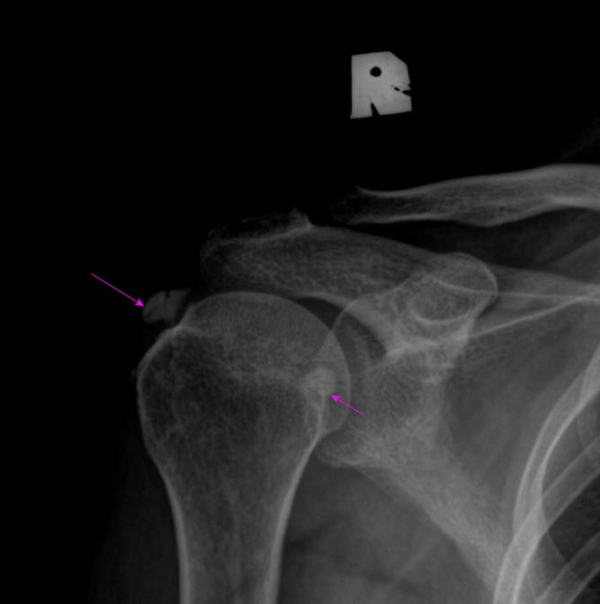

¹æ»ç¼± °Ë»ç :  ÃÊÁø ½Ã ¹æ»ç¼± °Ë»ç¿¡¼­ ¾çÃø ±Ø»ó°Ç°ú °ß°©Çϱٰǿ¡ Å« ¼®È¸°¡ °üÂûµÈ´Ù(»çÁø 8. 9).

Ä¡·á ÈÄ ¾à 1´Þ ÈÄ¿¡ ÃßÀû °Ë»çÇÑ »çÁø¿¡¼­  ¿ìÃø ±Ø»ó°Ç ¼®È¸´Â °ÅÀÇ ¼Ò½ÇµÈ ¸ð½ÀÀ̰í

ÁÂÃø ±Ø»ó°ÇÀÇ ¼®È¸´Â ¸¹ÀÌ ÁÙ¾îµç ¸ð½ÀÀÌ´Ù(»çÁø  10. 11).